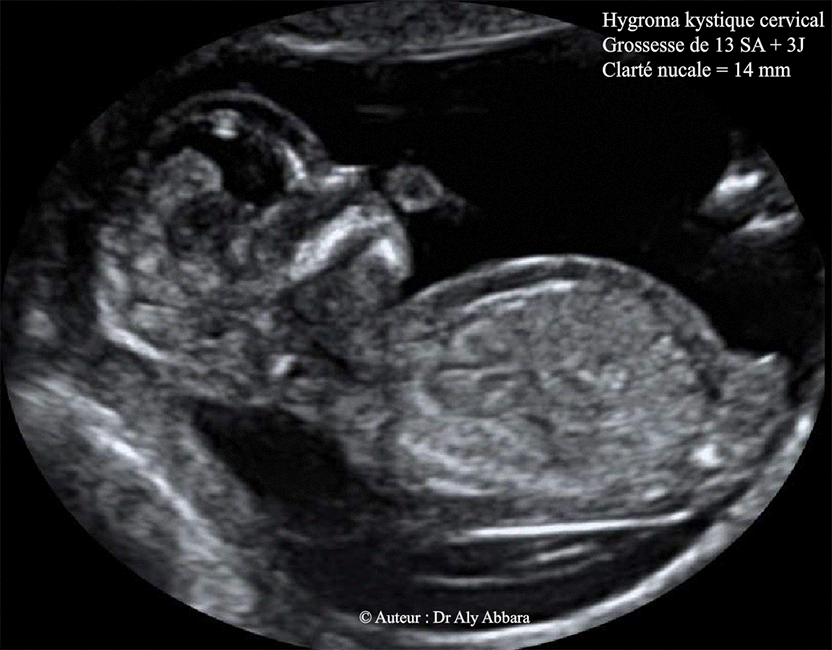

Découvrez les actes de chirurgie des fentes palatines (anciennement appelées Diagnostic : DAN • Echographie Deuxième trimestre • Fente labiale ou labio-palatine • Palais isolé : pas en routine Sonographic assessment of normal fetal palate using three-dimensional imaging: a new technique Aspect échographique anténatal des fentes Journée annuelle du CPDP Vendredi 04 octobre 2019 AS Weingertner Les malformations de la face

Fente labiopalatine ou bec de lièvre une malformation congénitale (2) AlloDocteurs. Forme unilatérale complète associe une ouverture du seuil narinaire, de la lèvre supérieure et de l'arcade alvéolaire jusqu'au canal palatin antérieur. Aspect échographique anténatal des fentes Journée annuelle du CPDP Vendredi 04 octobre 2019 AS Weingertner Les malformations de la face